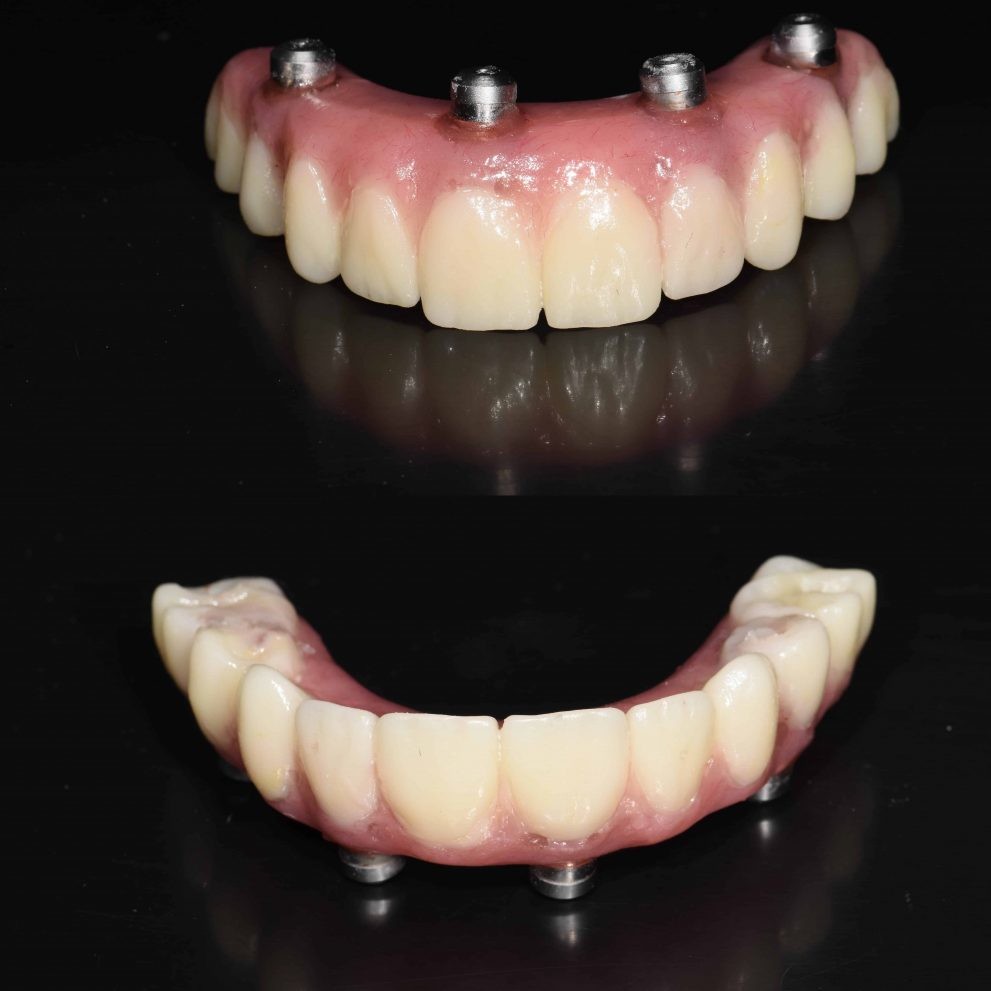

Yes it is possible to get a whole new set of teeth

Struggling with dental issues can be painful and stressful. If you’ve been dealing with tooth loss and wish you could have a new set of teeth, implant surgery can make this happen.

Dental implants have been in use for decades now and have an excellent track record. These teeth act just like your regular teeth so you have no food restrictions and they don’t need a complicated maintenance routine, just good oral hygiene practices and routine check-ups will suffice to keep them in good shape.

Can I have all my teeth pulled and get implants?

Yes, it is possible to get a whole new set of teeth. This is often the route chosen by those who have been dealing with dental distress for years.

Permanent dental implants are made with metals like titanium or zirconia. They are embedded well into the gum line and act just like the roots of your teeth. Replacement teeth are then affixed onto these implants. Dental implants can last a lifetime and are considered to be a permanent solution for tooth loss. All-on-four and all-on-six dental implant surgeries can be done to give you a new set of teeth in just one jaw or your entire mouthful of teeth.

The experienced dentists at Dental Artistry are able to insert implants in your jaw and fix in a whole new set of teeth that are anchored firmly by the implants. Not only are these a permanent, more efficient solution but they also prevent bone loss or erosion and the consequent sagging of the face often associated with dentures.

How many implants are needed for a full mouth?

Dental Artistry offers the option of giving you a full set of teeth with just four sets of implants. This surgical procedure is called all on four. One implant can hold in place multiple teeth. Sometimes your dentist may recommend that you have six implants instead of six, this is called the all on six procedure. Your dentist will advise how many implants are best for your needs.

How much is a full top set of dental implants?

Every mouth is different, and the final costing will depend on the specific procedures that need to be carried out for your teeth. An approximate costing for a full upper set of teeth would fall somewhere between NZ$18,000 and NZ $30,000. Learn more about the cost of dental implants. Dental Artistry offers finance options so you can book a consultation and discuss this.

How much does it cost to replace all your teeth?

The cost of replacing all your teeth is about double the cost of replacing a full set of your upper or lower jaw. While contemplating the financial investment, do take into account that these implants can last a lifetime and provide long-term benefits like preventing bone erosion, removing any diet restrictions (that you would otherwise have due with other forms of teeth replacement) and are easy to care for. Many who undergo this procedure comment on their newly regained confidence as well.